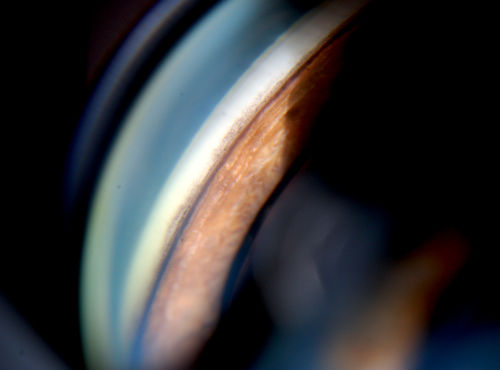

Gonioscopy; Scattered Peripheral Anterior Synechiae

Patient comes in for evaluation for glaucoma. Patient also has a history of Uveitis. Last flare up was back in 1990. Patient's VA was 20/30, Right eye and 20/40-1, Left eye. Slit Lamp Gonioscopy reveals iris bow with scattered PAS around the angles of the anterior chamber. You can also see pigmentation in the trabecular meshwork. Patient will follow up in 3-months.